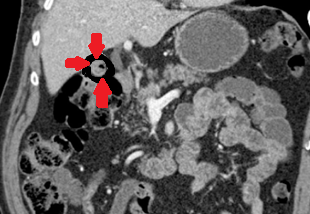

CT Angiography. Presence of a ruptured pseudoaneurysm of the common hepatic artery (Courtesy Dr. V. Penopoulos)